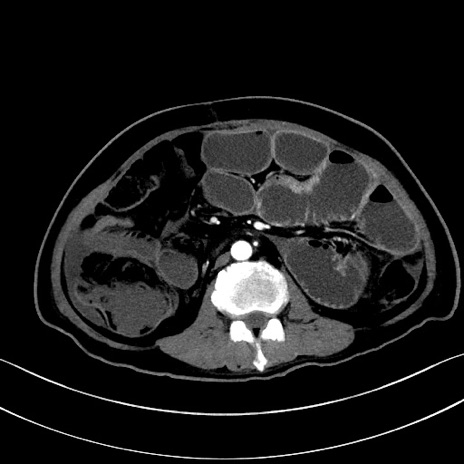

冠状断像

【症例】60歳代男性

【主訴】嘔吐

【現病歴】胃癌にて胃全摘後。食思不振が悪化し、夜中に嘔吐することがある。

【既往歴】胃癌、胃全摘、脾摘、胆摘後

【データ】WBC 5900、CRP 10.56